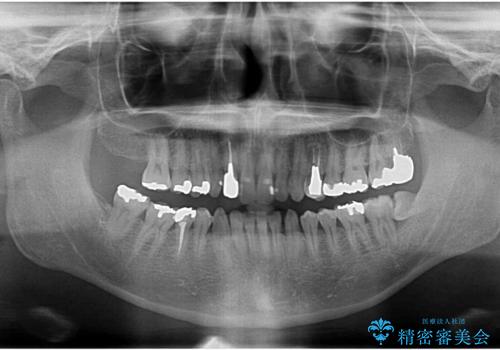

- 口をあけた時に目立つ銀歯を白くしたい、と来院されました。

治療する部位や銀歯の下に虫歯が再発していたかどうか、神経処置の有無等の条件によりセラミックインレー・クラウンにするかを判断し長期的に虫歯が再発しにくいような口腔内環境を目指します。

見た目の改善だけではなく、長期的に虫歯の再発を防ぎ自分の歯を守るために銀歯をはずし、セラミック修復物・補綴物による機能回復を行いました。